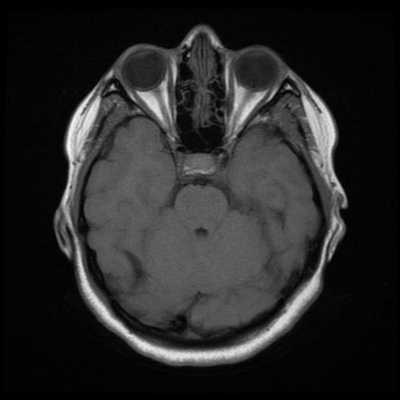

Классический пример МРТ снимков головного мозга показан на рисунках ниже. Магнитно-резонансная томография выполняется в поперечной (или аксиальной - рисунок снизу) и продольной (или сагиттальной — рисунок сверху) плоскостях.

Исследование выполняется в нескольких режимах. Основные из них Т1 и Т2. Изображения, полученные в данных режимах, часто также называют Т1-взвешенными или Т2-взвешенными снимками. Изображения, показанные выше, сделаны в Т1-режиме.

Главное отличие этих режимов - в том, как на снимках отображается жидкость и воздух. В Т1 режиме ткани, содержащие большое количество воды, имеют более темную окраску, в то время как в Т2 режиме они яркие, светлые. Это легко понять, посмотрев на снимки выше - глазные яблоки визуализируются в виде светлых парных округлых образований с одной стороны яркие и светлые, с другой - темные. Следовательно, снимок справа сделан в Т1 режиме, снимок слева - в Т2. Также существует разница в том, как в этих режимах отображается серое вещество головного мозга. В Т2 режиме оно светлее, чем белое вещество.